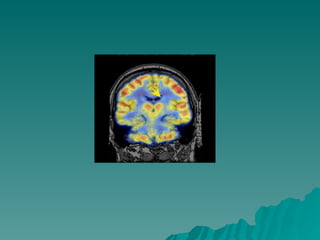

Caudate, Putamen, and Globus Pallidus Volume in Schizophrenia: A Quantitative MRI Study   Hiroto Hokama, M.D.1, Martha E. Shenton, Ph.D.1, Paul G. Nestor, Ph.D.1, Ron Kikinis, M.D.2, James J. Levitt, M.D.1, David Metcalf, M.A.2, Cynthia G. Wible, Ph.D.1, Brian F. O'Donnell, Ph.D.1, Ferenc A. Jolesz, M.D.2 and Robert W. McCarley, M.D.3 ABSTRACT Basal ganglia structures have been reported to be abnormal in schizophrenia, However, while component structures of the basal ganglia are functionally  differentiated, there have been no evaluations of their separate MRI volumes using small voxel (1.5 mm3) SPGR techniques and multi-plane assessments. We examined MRI scans from 15 male, right-handed neuroleptic-medicated schizophrenics and 15 age, handedness, and gender-matched normal controls. Compared to controls, schizophrenics showed enlarged volumes: 14.2% for total basal ganglia, 27.4% for globus pallidus, 15.9% for putamen and 9.5% for caudate. Increased volumes, especially caudate, were ssociated with poorer neuropsychological test performance on finger tapping and Hebb's Recurring Digits. These findings indicate abnormalities throughout all basal ganglia structures in at least a subgroup of schizophrenics

14.2% para o total dos ganglios da base; 27.4% para o globo pallido; 15.9% para o putamen – consistente com defeito na  neurogênese – fase de pruning; 9.5% para o caudate; O caudado pode estar reduzido em pacientes que  desenvolveram discinesia tardia comparado aos que não Desenvolveram; O Aumento do volume do  caudado, em especial, foi associado Com teste neuropsicológico pobre

Caudate, Putamen, andGlobus Pallidus Volume in Schizophrenia: A Quantitative MRI Study Hiroto Hokama, M.D.1, Martha E. Shenton, Ph.D.1, Paul G. Nestor, Ph.D.1, Ron Kikinis, M.D.2, James J. Levitt, M.D.1, David Metcalf, M.A.2, Cynthia G. Wible, Ph.D.1, Brian F. O'Donnell, Ph.D.1, Ferenc A. Jolesz, M.D.2 and Robert W. McCarley, M.D.3 ABSTRACT Basal ganglia structures have been reported to be abnormal in schizophrenia, However, while component structures of the basal ganglia are functionally differentiated, there have been no evaluations of their separate MRI volumes using small voxel (1.5 mm3) SPGR techniques and multi-plane assessments. We examined MRI scans from 15 male, right-handed neuroleptic-medicated schizophrenics and 15 age, handedness, and gender-matched normal controls. Compared to controls, schizophrenics showed enlarged volumes: 14.2% for total basal ganglia, 27.4% for globus pallidus, 15.9% for putamen and 9.5% for caudate. Increased volumes, especially caudate, were ssociated with poorer neuropsychological test performance on finger tapping and Hebb's Recurring Digits. These findings indicate abnormalities throughout all basal ganglia structures in at least a subgroup of schizophrenics

14.2% para ototal dos ganglios da base; 27.4% para o globo pallido; 15.9% para o putamen – consistente com defeito na neurogênese – fase de pruning; 9.5% para o caudate; O caudado pode estar reduzido em pacientes que desenvolveram discinesia tardia comparado aos que não Desenvolveram; O Aumento do volume do caudado, em especial, foi associado Com teste neuropsicológico pobre